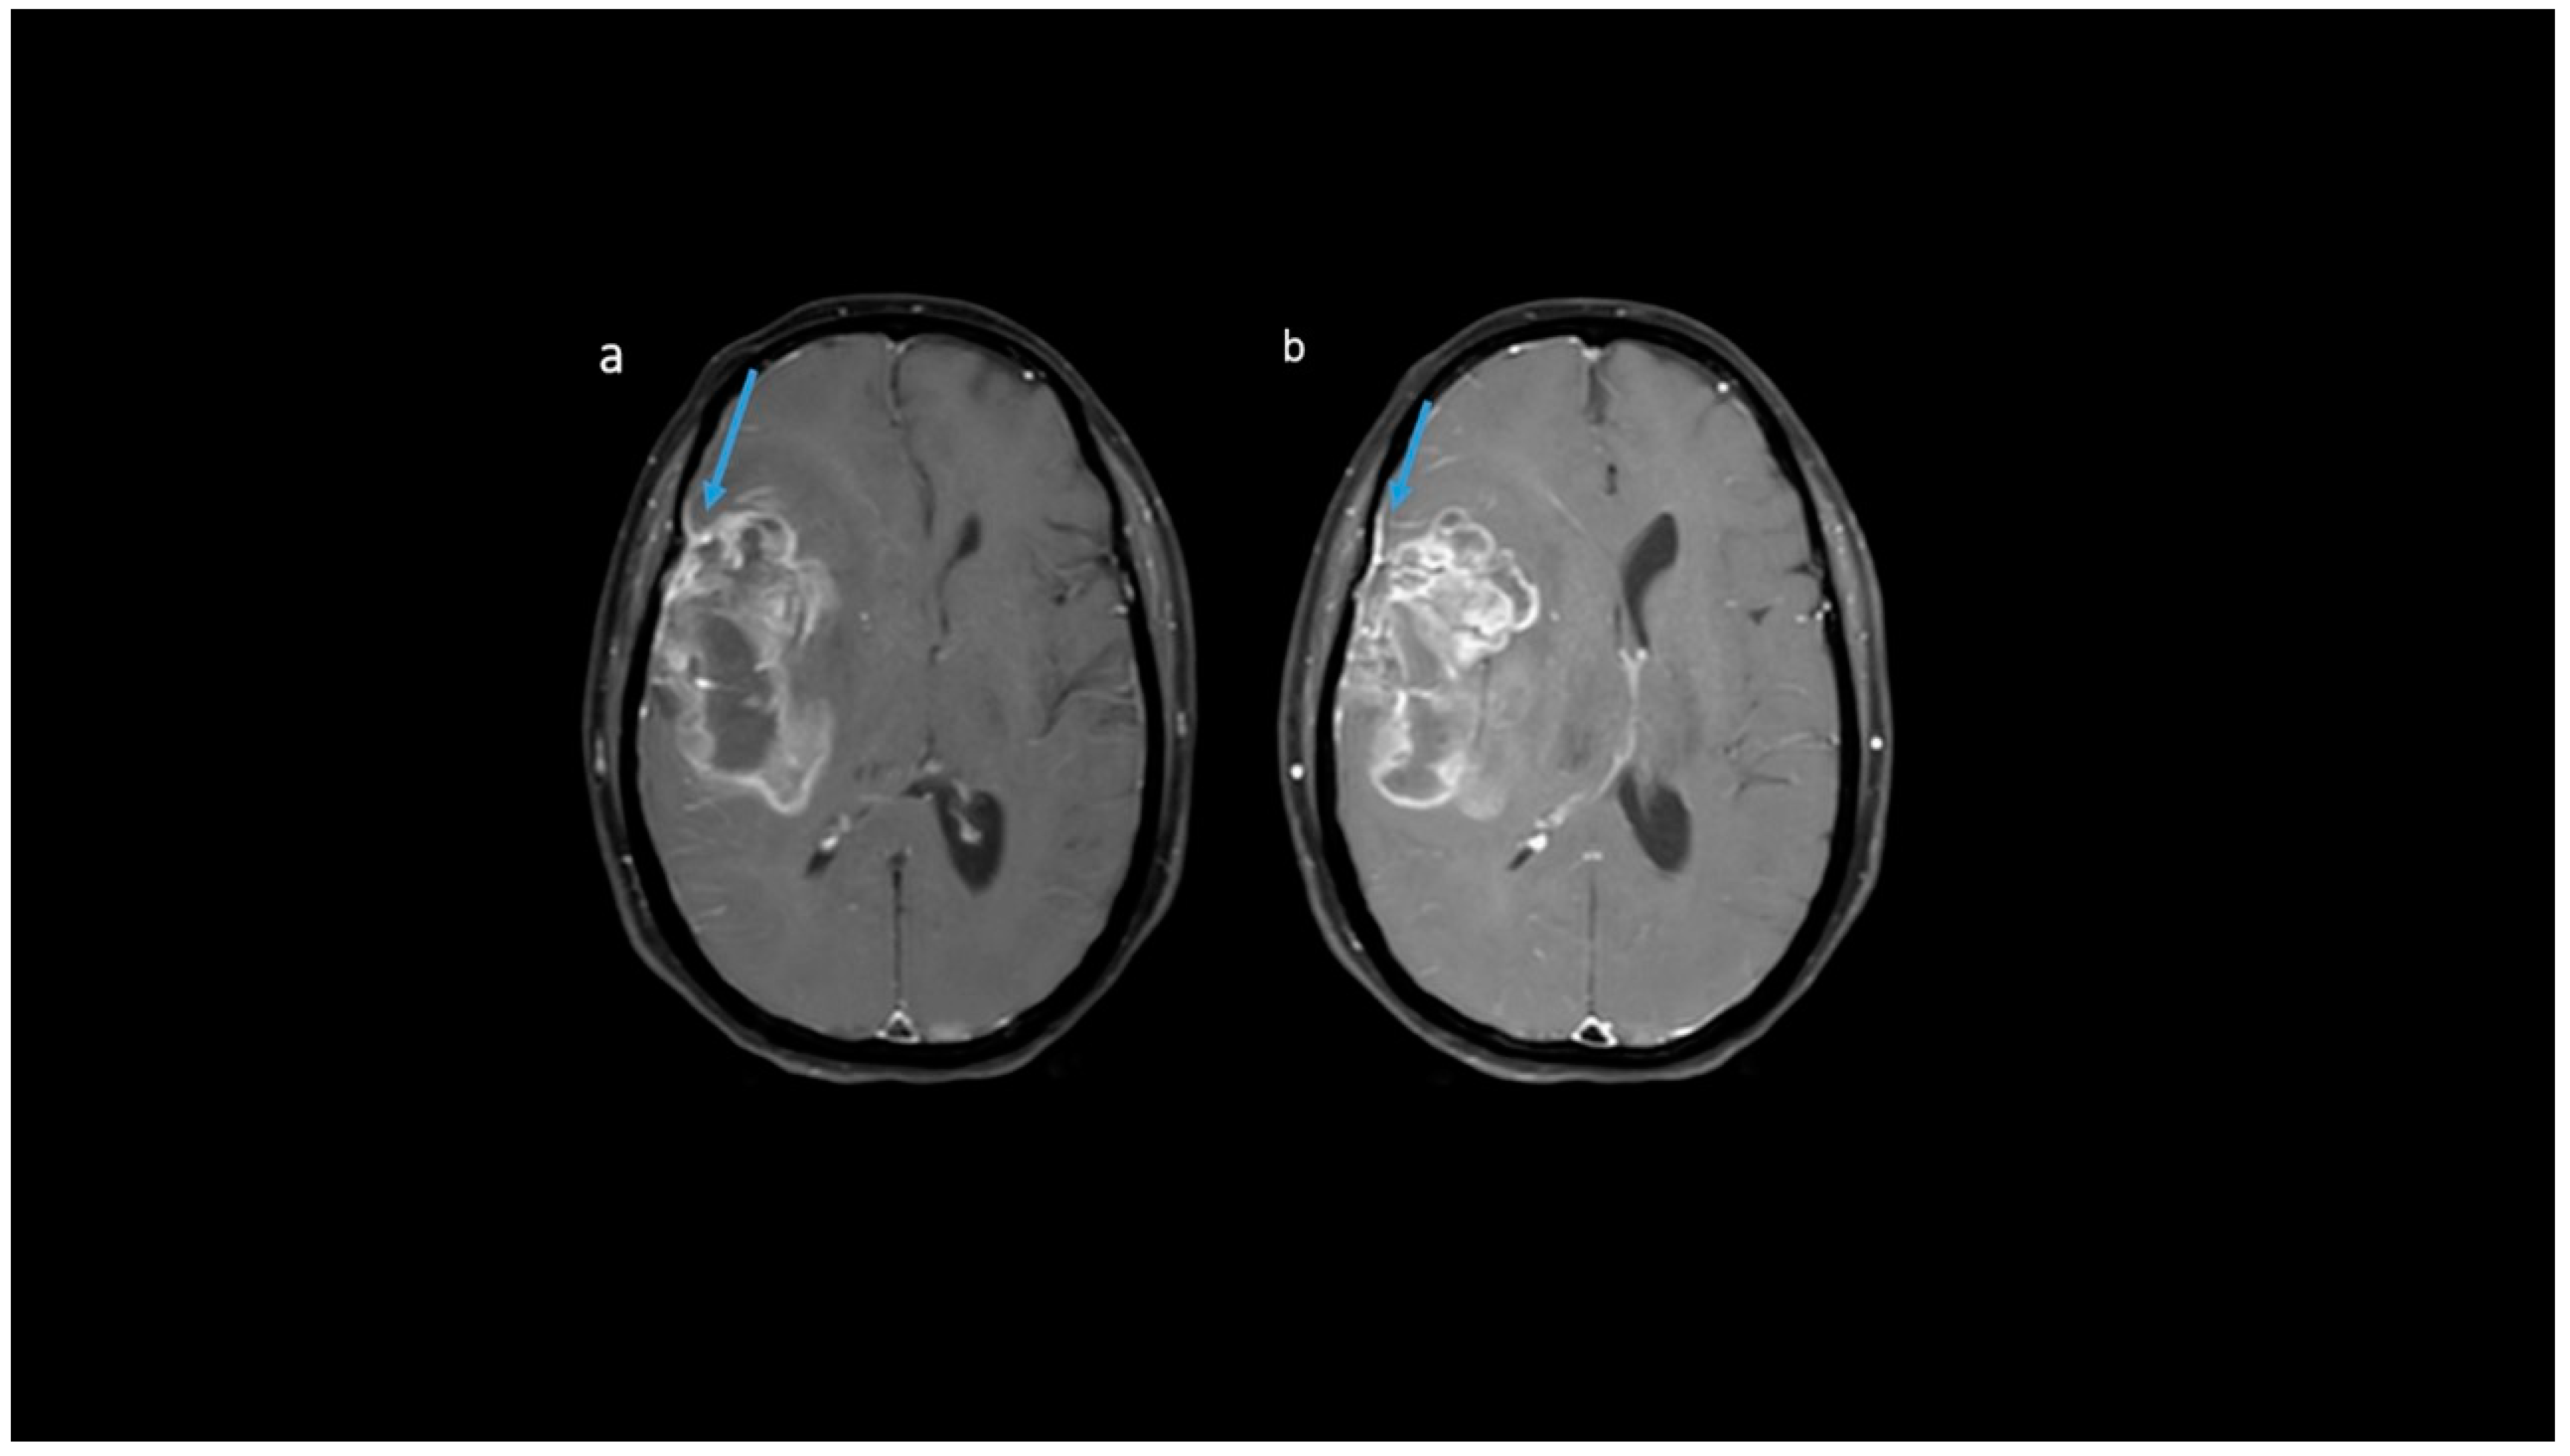

3.2. MRI Parameters of IDH-Wildtype vs. Mutant Phenotype Tumors

| Variable | Parameter | IDH-Mutated (n = 19) | IDH-Wildtype (n = 129) | p-Value |

|---|---|---|---|---|

| Enhancement I | Mild | 9 (47.4) | 5 (3.9) | <0.001 |

| Moderate | 6 (31.6) | 25 (19.4) | ||

| Severe | 4 (21.1) | 99 (76.7) | ||

| Enhancement III | Rim | 6 (31.6) | 104 (80.6) | <0.001 |

| Nodular | 0 | 2 (1.6) | ||

| Patchy | 11 (57.9) | 13 (10.1) | ||

| Solid | 2 (10.5) | 10 (7.8) | ||

| Necrosis | None | 3 (15.8) | 3 (2.3) | <0.001 |

| <25% | 11 (57.9) | 14 (10.9) | ||

| 25- 50% | 2 (10.5) | 35 (27.1) | ||

| >50% | 3 (15.8) | 77 (59.7) | ||

| Dural enhancement | AbsentPresent | 07 (70.0) | 31 (24.0)48 (52.7) | 0.013 |

| Edema | None | 3 (15.8) | 3 (2.3) | 0.025 |

| <tumor volume | 11 (57.9) | 68 (52.7) | ||

| Equal to tumor volume | 4 (21.1) | 35 (27.1) | ||

| >tumor volume | 1 (5.3) | 23 (17.8) | ||

| Cysts * | No | 11 (57.9) | 115 (89.1) | 0.001 |

| Yes | 6 (31.6) | 14 (10.9) | ||

| Subcortical involvement | Involved | 18 (94.7) | 94 (72.9) | 0.044 |

| Not involved | 1 (5.3) | 35 (27.1) | ||

| rCBV | Median (IQR) | 1.8 [1.4–2.0] | 2.6 [1.9–3.5] | 0.001 |